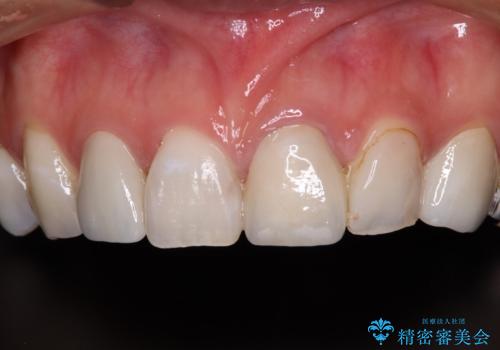

大きなむし歯と欠損をセラミックに 部分矯正を併用した総合歯科治療

- 長年むし歯を放置してしまっているとのことで来院された患者様です。

神経が除去されている歯、根管治療の必要な歯、むし歯の非常に大きな歯に対してオールセラミッククラウンにて補綴治療を行うこととしました。

途中通院されなかった時期が何度かあったため、初診から4年以上の年月がかかりましたが、比較的スムーズに治療を進めることができました。

下顎前歯の歯列を整えたことで、上顎前歯の咬み合わせが安定し、自然な口元に仕上げることができました。